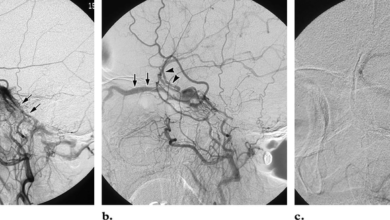

Dural arteriovenöz fistüller (dural avf, davf)

Dural arteriovenöz fistül (Dural AVF) nedir? Dural arteriovenöz fistüller (Dural AVF’ler), beyni saran ve dura denen tabaka yüzeyindeki arterler (atardamar)…